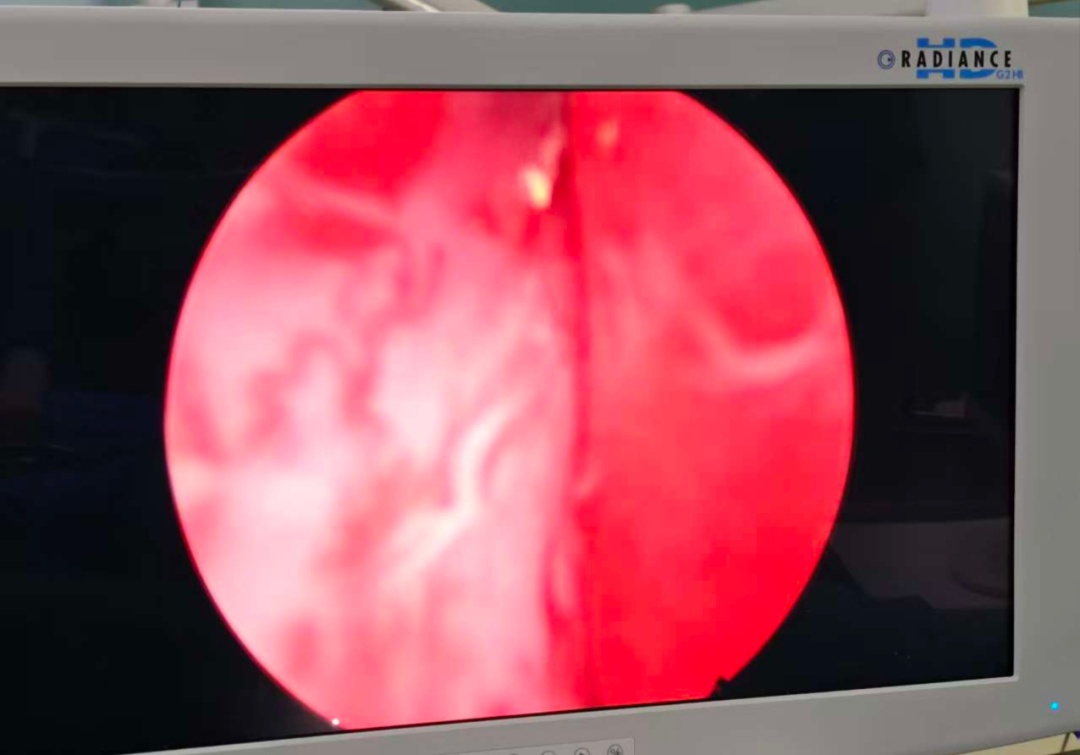

病情介绍 患者张先生(化名),77岁,因“尿频、尿急、尿痛伴血尿1天”来我院急诊。患者痛苦面容,自觉排尿困难且伴有肉眼可见的红色尿液,严重影响生活质量。 经检查发现,患者存在以下泌尿系统问题: 1.右侧输尿管结石伴有肾积水和感染 2.膀胱多发结石 3.前列腺增生 这些疾病相互影响,形成恶性循环:前列腺增生导致排尿不畅,尿液滞留形成膀胱结石;膀胱结石又可能堵塞尿道出口,加重排尿困难;而输尿管结石则阻碍尿液从肾脏排出,引起肾积水和感染,严重时可能影响肾功能甚至导致败血症。 治疗过程 面对这一复杂情况,区中医医院泌尿外科团队制定分期手术方案,确保治疗安全有效: 第一期手术:急诊处理,解除危机 手术名称:经尿道输尿管镜下膀胱结石钬激光碎石取石术+右侧输尿管支架置入术(双J管置入) 手术目的: 1.解除感染隐患:置入输尿管支架管,能立即疏通梗阻的右侧输尿管,引流出淤积的感染尿液,迅速控制感染,保护肾功能。 2.清除膀胱结石:同时处理已存在的膀胱结石,缓解部分下尿路症状。 此次手术快速、微创,核心目标是“控制感染、引流减压”,为后续根治性手术创造安全的身体条件和手术窗口期。 第二期手术:根治性处理,经过近两周的抗感染治疗和身体恢复,患者一般情况显著改善。 手术名称:经尿道右侧输尿管镜钬激光碎石取石术+前列腺电切术(TURP)+经尿道右侧输尿管支架置换术 手术目的: 1.粉碎输尿管结石:在支架管引导下,精准粉碎并取出造成梗阻的“元凶”——右侧输尿管结石。 2.切除前列腺:彻底切除增生的前列腺组织,从根源上解除下尿路梗阻,预防结石复发。 3.更换支架:确保输尿管通畅愈合。此次手术一举解决了所有根本性问题。 术后恢复 术后患者恢复顺利: 1.血尿、尿痛等症状消失。 2.困扰已久的尿频、尿急、夜尿增多等症状得到极大改善。 3.复查尿流率检查,结果完全恢复正常。 4.患者对治疗效果非常满意,由衷感谢我科团队精湛的技术和负责任的决策。 此次手术的成功,体现区中医医院处理复杂高危病例的丰富经验和先进理念: 1.精准决策:不盲目追求“一刀切”,而是根据“轻重缓急”原则,制定个体化的分期治疗方案。先解决急性、危及生命的问题(感染梗阻),再处理慢性、根源性问题(结石、前列腺增生),最大程度保障了患者安全。 2.技术的保障:两次手术均采用经尿道的微创方式,利用输尿管镜、电切镜等先进设备,体表无切口,创伤小,恢复快,非常适合高龄患者。 3.围术期管理:完善的术前准备、术中的麻醉配合、细致的术后护理,是患者能够平稳度过两次手术、顺利康复的坚实基础。 奉贤区中医医院 泌尿外科团队 专家提醒,老年男性出现以下症状时应及时就医: ·尿频、尿急、夜尿增多 ·排尿困难、尿流变细 ·血尿 ·腰背部疼痛 早期诊断和合理治疗能够有效保护肾功能,提高生活质量。我院泌尿外科在此类复杂泌尿系统疾病的微创治疗方面积累了丰富经验,为众多患者解除病痛。 王志伟 副主任医师 泌尿外科王志伟副主任医师,毕业于南昌大学医学院,医学硕士。2017年至上海长海医院泌尿外科进修学习、2022年至南昌大学第二附属医院泌尿外科进修学习。获2020年度医院十大好医生、医院优秀员工。主持完成市级科研课题2项,参与完成省级科研课题1项,两篇论文获得市级科协优秀学术论文二等奖。 擅长泌尿系统结石微创治疗,输尿管镜碎石取石术,电子输尿管软镜钬激光碎石负压取石术,彩超引导下经皮肾镜碎石取石术,泌尿系统感染的综合治疗,彩超引导下经会阴前列腺穿刺活检,前列腺增生微创手术,肾囊肿、肾肿瘤及前列腺肿瘤、膀胱肿瘤等泌尿系统肿瘤的诊治及微创手术治疗,及男性生殖相关疾病的诊治。 门诊时间 泌尿专科门诊: 周一全天,周二、周四、周五上午 王志伟副主任医师专家门诊: 周一上午、周三全天 便民咨询电话:57420861-8074